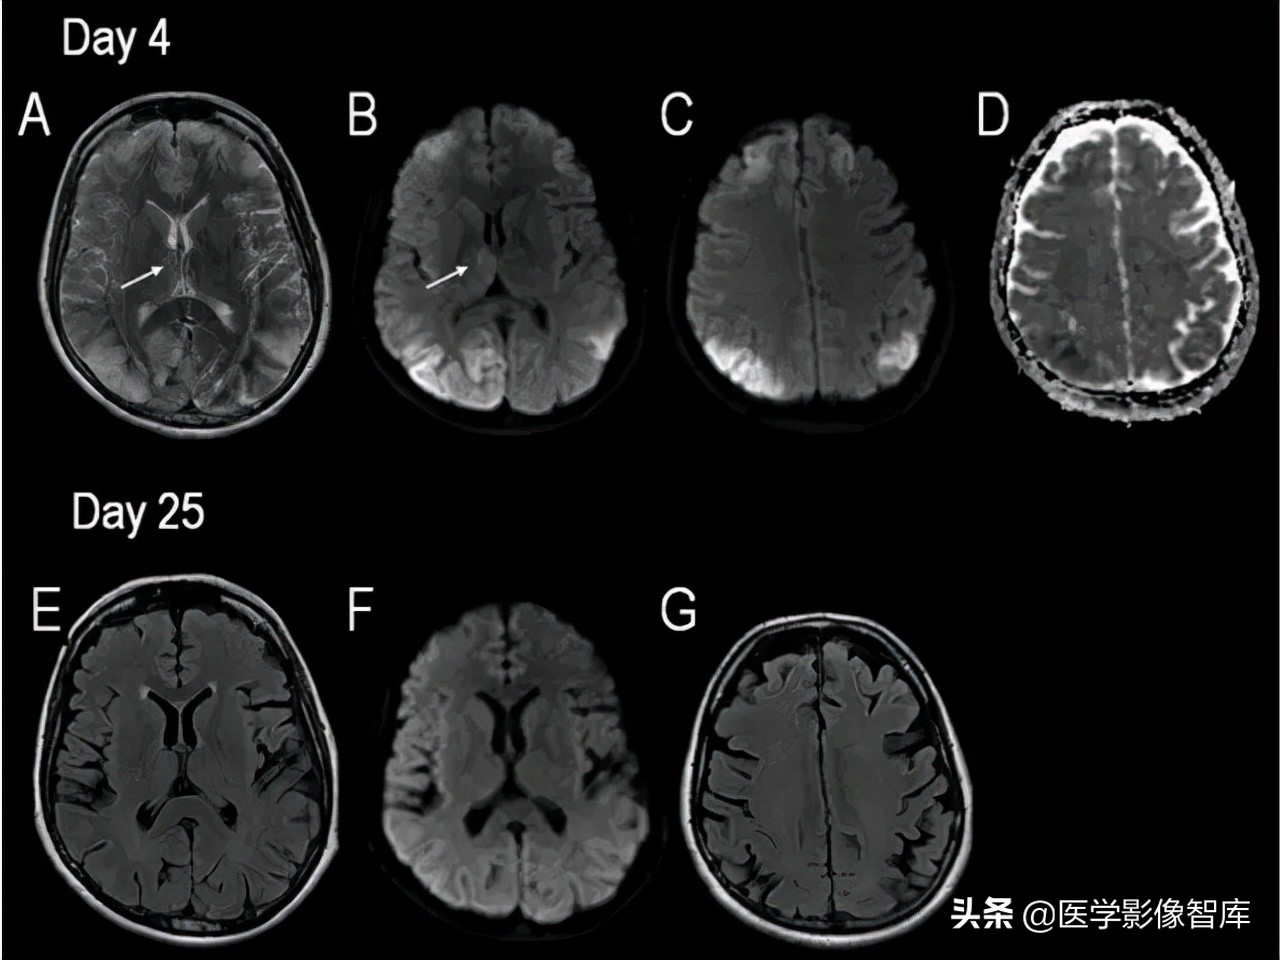

对于有明确癫痫发作病史的患者,癫痫介导的脑部影像学改变需要考虑,不同于癫痫的病因(肿瘤、FCD 等),癫痫介导的脑部影像学改变往往是可逆的,磁共振上大多表现为 T2WI 高信号,约半数表现为 DWI 高信号,常见的受累部位包括皮层 / 皮层下、基底节区、白质、胼胝体、小脑,而临床上无其他特异性的表现,如图 2 所示。

图 2 42 岁女性,延长的亚临床癫痫持续状态患者所做的两次头颅 MR 结果。A 为 T2WI,B、C、F 为 DWI,D 为 ADC 图,E、G 为 FLAIR,可见发病 4 天时双侧顶枕叶可见明显 DWI 高信号病灶,T2 相也为高信号,ADC 低信号,发病 25 天时,病灶消失